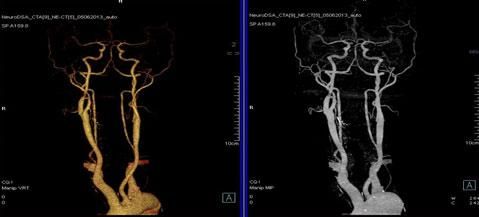

二、多層螺旋CT頭頸部及體部血管成像技術:

該機掃描覆蓋範圍廣、時間短,多種後處理分析軟件能顯示各血管細小分支,可以清晰顯示動脈瘤、動脈夾層、血管畸形、血管狹窄及動脈粥樣硬化斑塊等,适用于頭頸部血管成像、肺動脈成像、胸腹部血管成像及四肢血管成像。

1.顱腦血管成像:

動脈瘤

2、頸部血管成像